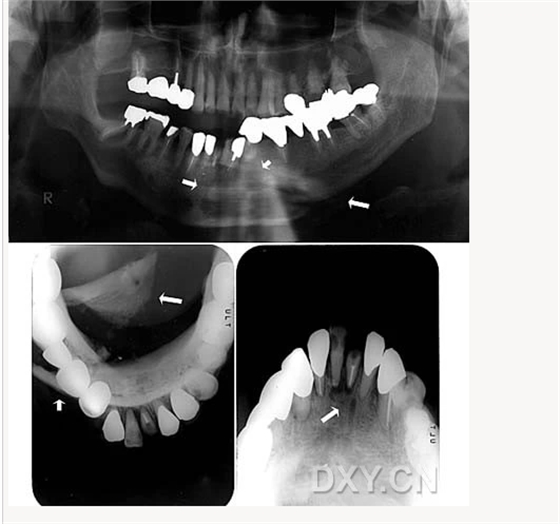

成釉細胞瘤